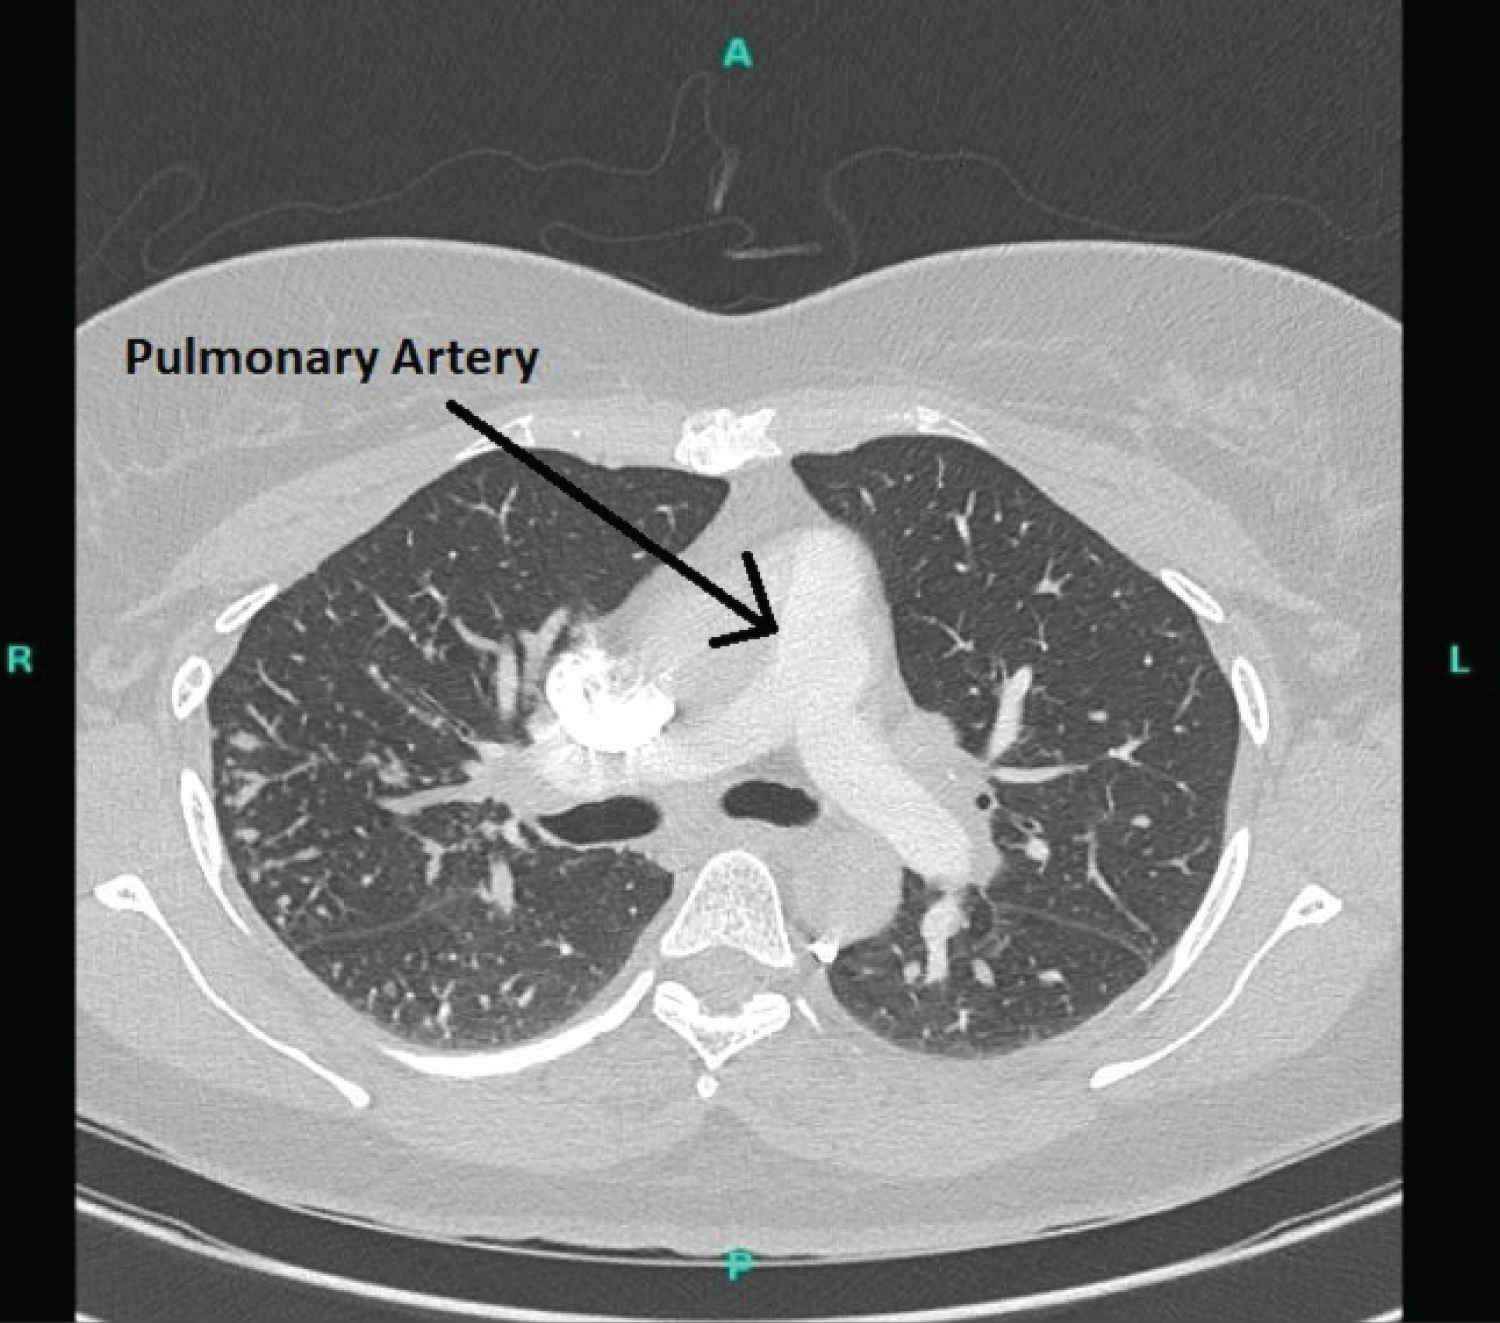

CT chest, abdomen, and pelvis showed multifocal nodular lung infiltrates, right upper lobe predominant with peripheral confluence/consolidation in conjunction with multi-station lymphadenopathy, worse in the mediastinum/hila raising the strong possibility of sarcoidosis, for which tissue sampling was advised. Borderline cardiomegaly with patent central, main, and segmental pulmonary artery lacking any evidence of acute or chronic pulmonary embolism. The spleen was normal in size with several indeterminate lesions raising the possibility of sarcoidosis. Several indeterminate hepatic lesions were found which could be hemangiomata, for which contrast-enhanced MRI was suggested. It was suggested that alternatively, these findings could be due to lymphoma or metastatic disease of indeterminate primary source. But no evidence of lymphoma or primary tumor could be found on CBC, mammogram, abdominal or pelvic imaging. MRI confirmed hepatic hemangiomata, splenic lesions. Bronchoscopic biopsy of the lesion from the right lung showed findings consistent with sarcoidosis. Based upon the radiological evidence and Siltzbach classification system, the patient was having stage II disease and was started on albuterol for symptomatic SOB, and steroid for sarcoidosis control. Eliquis was continued with all the precautions for falls. Referral to hematologist was provided for evaluation and assessment of low Protein S activity. Further plan for a follow-up assessment after 6 months to document disease status was planned (Figure 1, Figure 2, Figure 3 and Figure 4).

Figure 2: CT chest showing pulmonary artery. View Figure 2